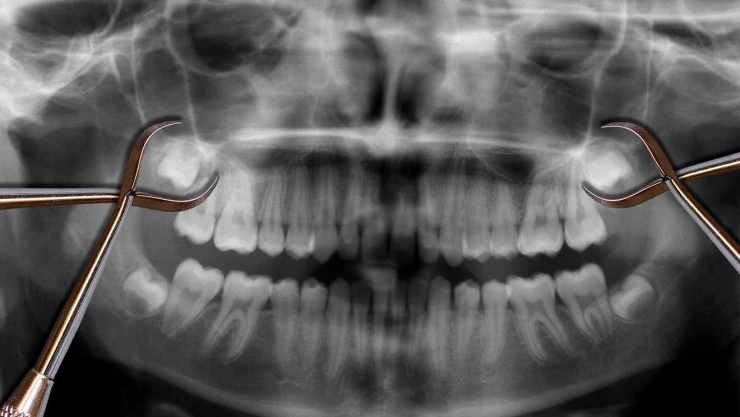

El especialista señala que cuando tratan de hacer erupción, estas vienen cubiertas por un epitelio especializado, el cual ese criterio está formando al diente y si esa "capita", en la radiografía se ve como negra, "eso puede ser un asiento o lo que puede llegar a producir un quiste o un tumor importante en la mandíbula".

La extracción de las muelas del juicio se recomienda en casos en los que se presenten problemas o se estime que puedan presentarse en el futuro. Según la UNAM, es importante acudir a un dentista para evaluar la necesidad de extraer las muelas del juicio y determinar el momento adecuado para realizar el procedimiento. En general, se recomienda la extracción temprana, antes de que las muelas del juicio hayan causado complicaciones significativas.

Las muelas del juicio suelen presentar problemas debido a que no tienen suficiente espacio para emerger correctamente. Esto puede resultar en una serie de complicaciones, como la impactación de las muelas, infecciones, daño a los dientes adyacentes y dolor intenso. Además, su posición en la parte posterior de la boca dificulta su limpieza adecuada, lo que aumenta el riesgo de caries y enfermedades periodontales.